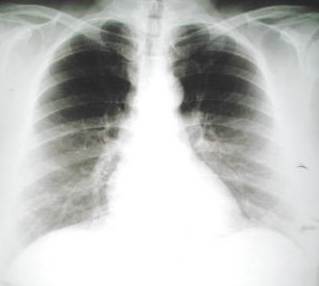

Radiografía del tórax

Tomografía torácica